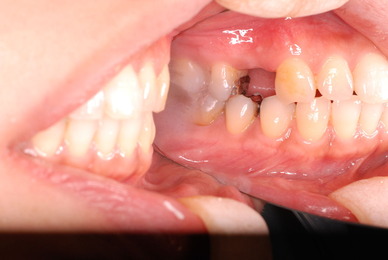

神経が死んでしまった歯は脆いのです。

重症の歯周病で削って上の歯とぶつからないようにしていた歯ですが

いつの間にか神経が死に歯の中が腐っていたようです。

それでヒビが入り割れてしまいました。